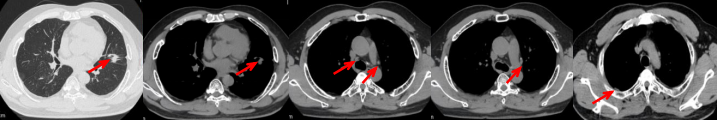

55岁男性,无吸烟史,有饮酒嗜好。2024年11月常规体检胸CT:左肺上叶占位性病变,大小约2.7×2.4cm,恶性可能大;左肺、左侧叶间胸膜及胸膜下多发微小结节,转移待除外。左侧胸腔积液,部分骨质改变。2024年12月初肺穿刺活检,病理:(肺)腺癌。NGS基因检测:CCDC6-RET(exon1-exon12)融合突变阳性(丰度:13.21%)。PD-L1表达阳性(TPS=35%,CPS=45)。

治疗经过:2025.01开始口服普拉替尼(400mg,qd)。2025.03复查胸CT:左肺上叶、右肺上叶、左肺斜裂见多发实性结节影,长径范围约3-17mm,较大者大小约17mm×12mm,位于左肺上叶下舌段,可见分叶、毛刺、胸膜凹陷、棘状突起征象。纵隔内小淋巴结。评效PR,随访中。治疗期间未出现毒性反应。

2024.12

2025.03评效PR